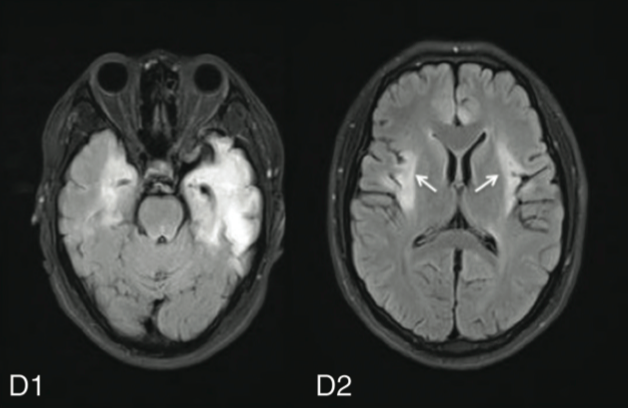

A頭部ct,mri所見 ウイルス薬を 画像検査では,側頭葉内側面,島回皮質を中 心に炎症や出血を示唆する信号異常が観察され ます.病変は一側性のことも両側性のこともあ りますが,両側性の場合は必ず左右差がありま す 図1単純ヘルペス脳炎の頭部mriと,非ヘルペス性急性辺縁系脳炎(non‒herpetic acute limbic encephalitis:NHALE) の増加に加えて,髄液NMDA型GluR抗体高値が参考となる.MRI異常は30~40% にみられ,記憶認知の後遺症が残りやすい.筆者らの厚生労働科学研究などにより, NHALE診断スキームが整い周知され,早期診断治療が可能とMri症例集 (a)中枢神経系(脳、脊髄) ヘルペス脳炎 (法典クリニックのご好意による) アルツハイマー型痴呆症 髄液拍動(cine画像) 脳炎(flair画像、拡散強調画像) 肝性脳症:t1強調横断画像 後頭蓋窩くも膜嚢胞:flair横断画像 (b)頭頚部 甲状腺癌(t2強調矢状断画像) 甲状腺腺腫、未

目でみる症例 単純ヘルペス脳炎 非ヘルペス性急性辺縁系脳炎 臨床雑誌内科 105巻1号 医書 Jp